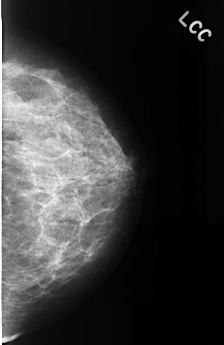

ics_version 1.0 filename C-0333-1 DATE_OF_STUDY 22 12 1995 PATIENT_AGE 44 FILM FILM_TYPE REGULAR DENSITY 2 DATE_DIGITIZED 12 10 1998 DIGITIZER LUMISYS LASER SEQUENCE LEFT_CC LINES 4480 PIXELS_PER_LINE 2904 BITS_PER_PIXEL 12 RESOLUTION 50 NON_OVERLAY LEFT_MLO LINES 4368 PIXELS_PER_LINE 2856 BITS_PER_PIXEL 12 RESOLUTION 50 NON_OVERLAY RIGHT_CC LINES 4456 PIXELS_PER_LINE 2864 BITS_PER_PIXEL 12 RESOLUTION 50 OVERLAY RIGHT_MLO LINES 4424 PIXELS_PER_LINE 2864 BITS_PER_PIXEL 12 RESOLUTION 50 OVERLAY |